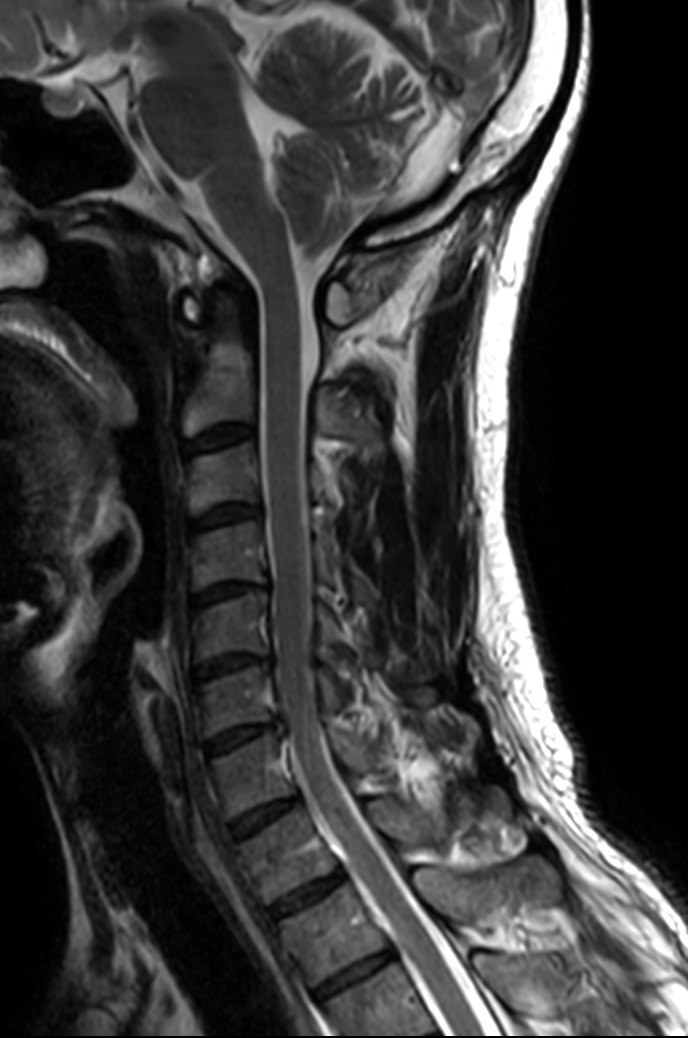

Sagittal T2w TSE

Sagittal T2w TSE - Compressed SENSE